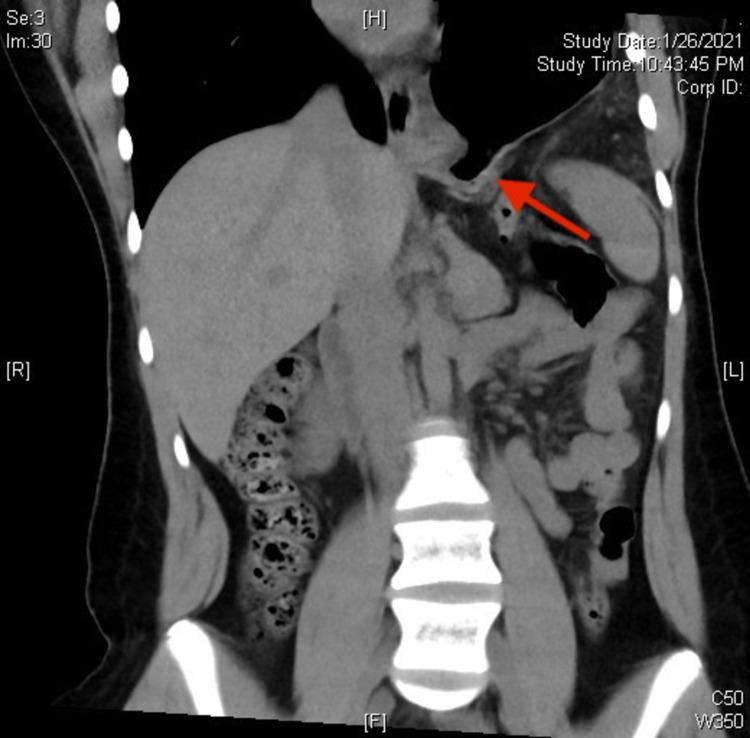

A 15-Year-Old Female Presenting With Traumatic Diaphragmatic Hernia One Year After a Car Accident.

Traumatic diaphragmatic hernia (TDH) is a known complication in patients with abdominal injuries. Delayed TDH, which presents long after the traumatic event, is a rare subset and is often missed upon initial presentation. We discuss a case involving a 15-year-old female who presented with persistent nausea, vomiting, and epigastric pain and was subsequently diagnosed with TDH via chest x-ray, later confirmed by CT scan. Further investigation of the patient's history revealed a motor vehicle accident one year prior in which the patient sustained an injury to the left chest. A chest x-ray at that time did not show signs of a diaphragmatic hernia. Surgical evaluation of the diaphragmatic defect further supported previous trauma as the mechanism of injury. Our patient's presentation is particularly interesting considering the lack of TDH reported in the pediatric population, as well as the presenting complaints being primarily gastrointestinal rather than respiratory.